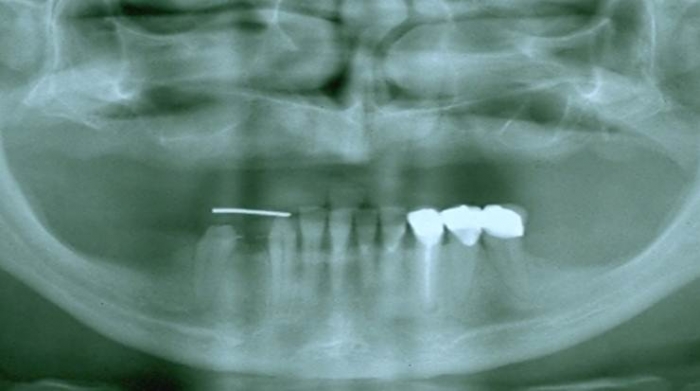

Raio X inicial